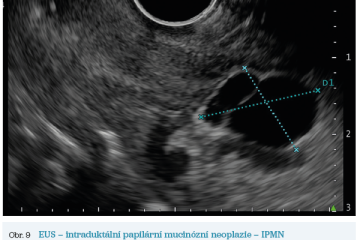

EUS umožňuje přesné vyšetření pankreatu. Lze také identifikovat a vyšetřit regionální lymfatické uzliny a vztah pankreatických lézí k okolním cévním strukturám. EUS může také sloužit jako navigace k odběru bioptického materiálu k cytologickému a histologickému vyšetření.21 AI je zde využívána k potvrzení malignity v IPMN. Kuwahara a kol. dosáhli s využitím 3 970 snímků a CNN algoritmu velké úspěšnosti v diferenciaci benigní a maligní IPMN s AUC 0,98.22 Řada studií se již zabývala AI asistovaným rozlišením chronické pankreatitidy a karcinomu pankreatu s AUC 0,940–0,986.23,24 Velká studie obsahující 1 174 461 snímků z celkem 583 případů hodnotící rozlišení autoimunitní pankreatitidy, karcinomu pankreatu, chronické pankreatitidy a normálního pankreatu dosáhla pro karcinom pankreatu AUC 0,97625 (obr. 6–9).